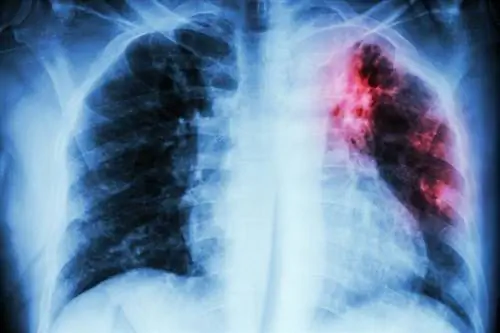

3/8 Туберкулез

Туберкулез

Туберкулез называли чахоткой. Проявляется утомляемостью, стойким субфебрилитетом, кашлем, а в запущенной стадии - кровохарканьем. Ей дали легенду о «романтической болезни» из-за того, что артисты часто ею болели. Эта болезнь известна с древних времен, но наибольшие потери она нанесла в восемнадцатом и девятнадцатом веках. Во время промышленной революции в Британии на долю туберкулеза приходилось до трети всех зарегистрированных смертей в периоды обострения эпидемии в течение нескольких лет. В 1921 г. была изобретена вакцина против микобактерий туберкулеза, а в 1946 г.на рынок были выведены первые эффективные препараты от заболевания, вызываемого этой бактерией. Сегодня люди, живущие в странах с бедностью, плохими санитарными условиями и плохим профилактическим медицинским обслуживанием, больше всего рискуют заболеть туберкулезом.